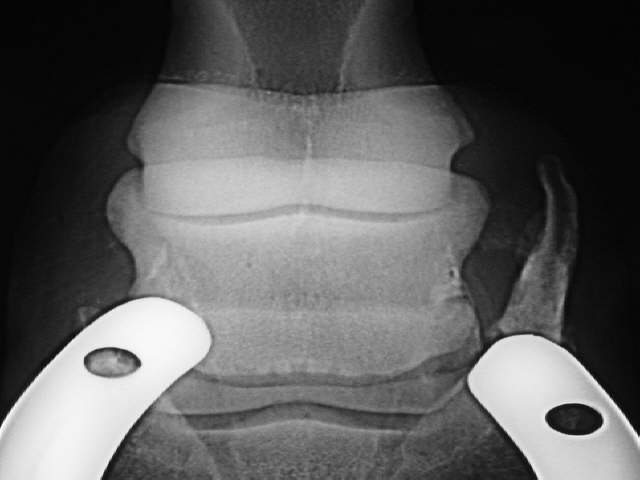

Rechts massive Hufknorpelverknöcherung